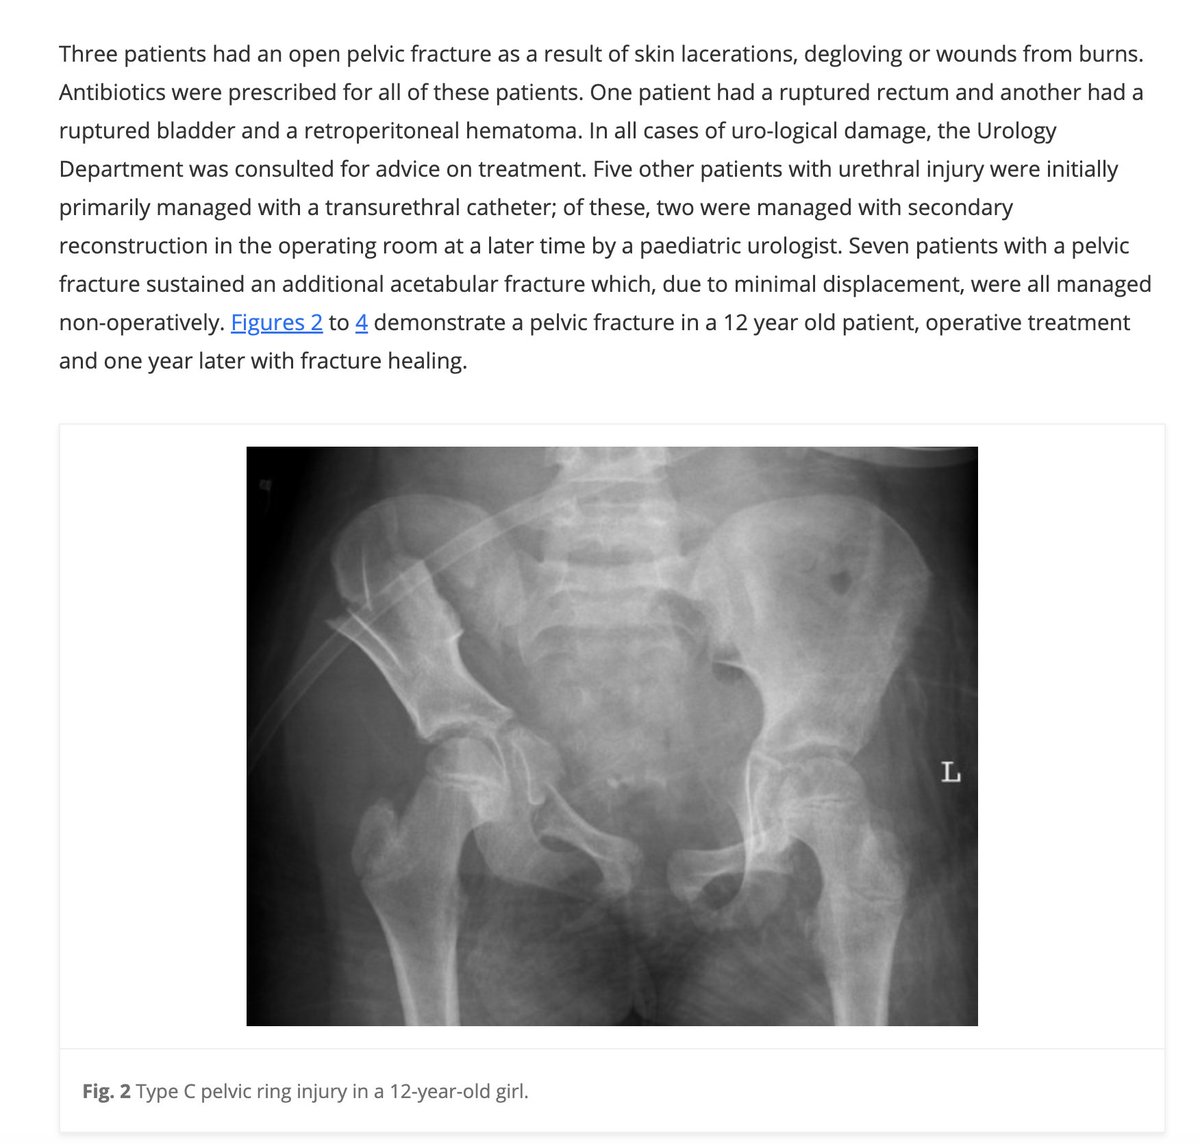

And finally, the video shows us these two X-rays as evidence that Alicia Brown has become paralyzed.

Both of these supposed Alicia Brown X-rays have been lifted from medical research journals on the internet and can be found via reverse image search. Here they are:

https://journals.sagepub.com/doi/10.1302/1863-2548-11-160138